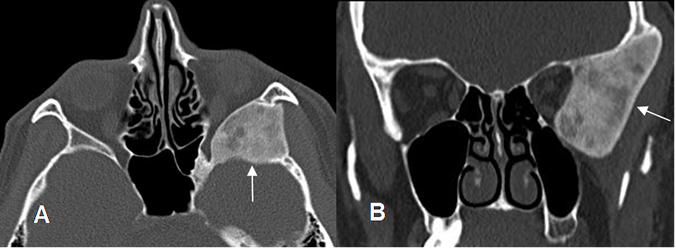

A: TAC axial y B: TAC reconstrucción coronal. Reborde lateral de la órbita y hueso cigomático engrosados y escleróticos, por enfermedad de Paget.

Fig 52. Enfermedad de Paget fase esclerótica.